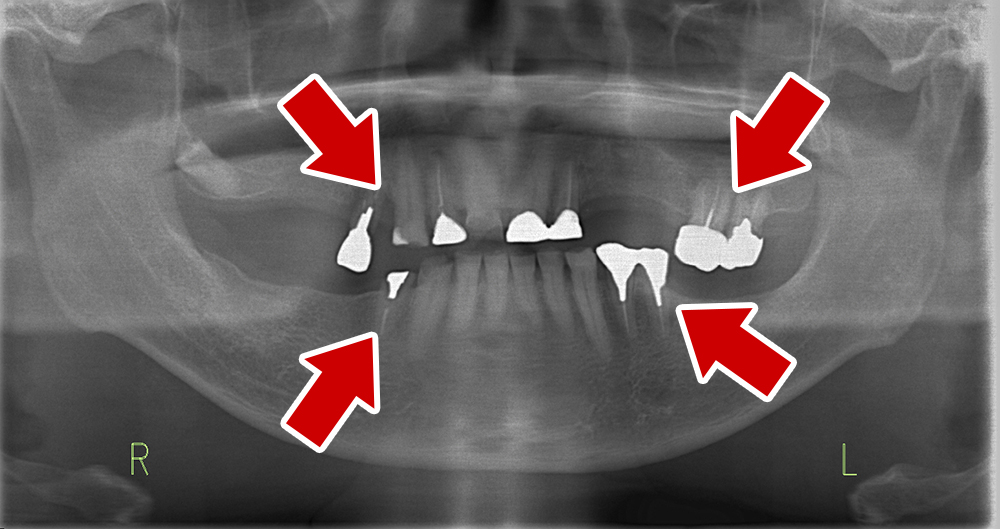

55歳 男性

- 主訴

- 前歯でしか咬めなく、食事を採るのに非常に困難で辛い

- 処置内容

- 上顎6本、下顎3本

- 治療費用

- 上顎:約230万(税込)下顎:約120万(税込)

- 治療期間

- 上顎:1年(仮歯まで8か月)下顎:8か月(仮歯まで5か月)

- リスク

- 上部構造物、仮歯の破折、術後の腫れ(3日)、人工歯根脱落リスクがあります